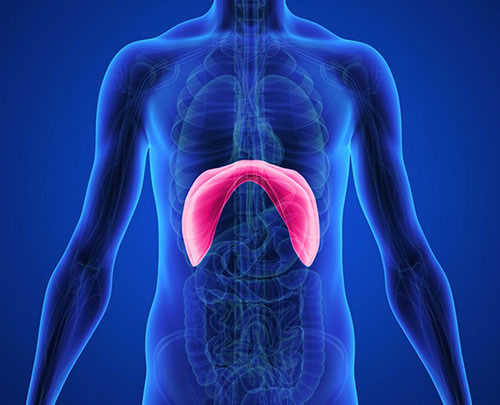

Eventração Diafragmática

A Eventração Diafragmática é uma condição caracterizada pela elevação da cúpula do diafragma